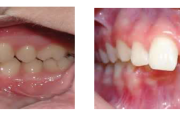

Normaalse jäävhammaskonna pilt küljelt ja eest vaadatuna.